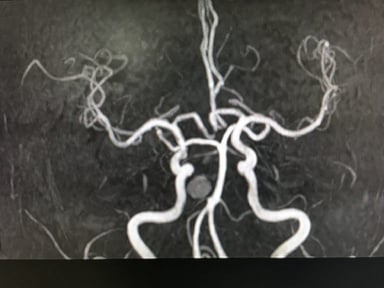

Thường gặp ở giới trẻ nhiều hơn, đặc biệt là những người đã từng bị đột quỵ. Đột quỵ không rõ nguyên nhân thường diễn ra một cách thầm lặng nhưng vẫn làm tổn thương não. Đôi khi được vô tình phát hiện thông qua việc sử dụng hình ảnh chẩn đoán hệ thần kinh như chụp cộng hưởng từ MRI não (sọ não và mạch não).